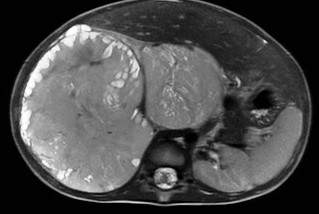

Wilms tumor. It is the most common kidney tumor in childhood that appears between 2-5 years of age. It is usually only noted when the tumor is palpable as an abdominal mass. Hematuria, hypertension, vomiting and abdominal pain are also part of the clinical picture. US examination is a basic method in both the diagnostics and the follow-up of the tumor. The tumor is normally seen as a homogenous or an inhomogeneous mass, dislocating the pyelon and the surrounding retroperitoneal blood vessels. It is important to rule out any lesion in the other kidney. MRI examination: gives a picture of the entire abdomen, kidneys included. Nodal metastases, tumor thrombus are well depictable. CT-examination: is to be chosen if MRI is not available. The tumor shows an inhomogeneous contrast enhancement and pulmonary metastases (invisible to x-ray examination) are also depictable.

Image

27. A solid, echogenic mass arising from the right kidney. Wilms tumor. Abdominal US.

28. MRI examination axial, T2weighted sequence. A solid mass arising from the right kidney and filling out the right side of the abdomen, with peripheral follicular cystic components. Wilms tumor. (with the courtesy of Dr. Gábor Rudas)